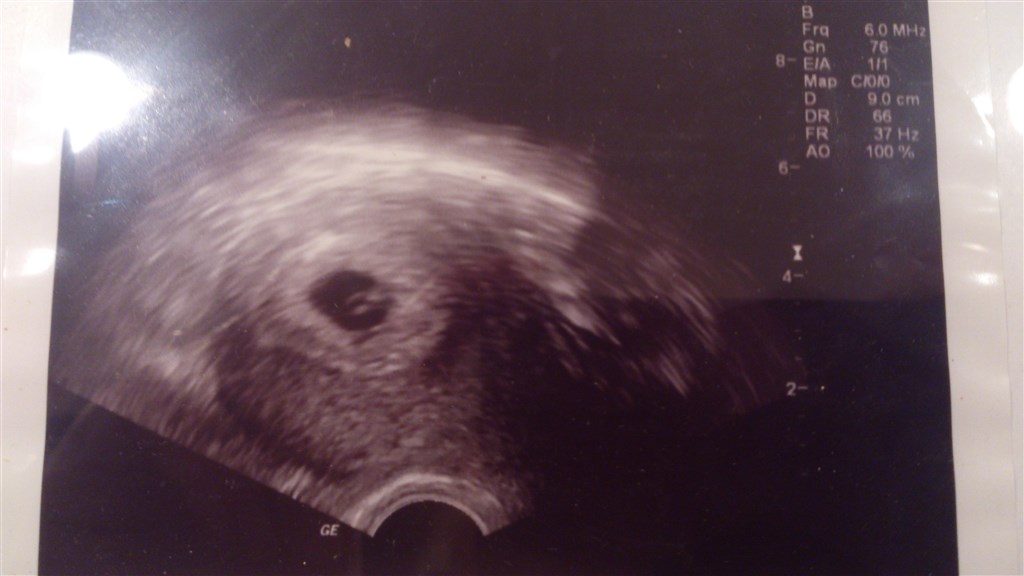

Efter min egen beregning er jeg 6+3 men hun kunne ikke terminberegne endnu så skal scannes igen om 14 dage så hun kan fastslå termin. Men hun mente at det nok passede meget godt med hvad jeg selv havde regnet mig frem til